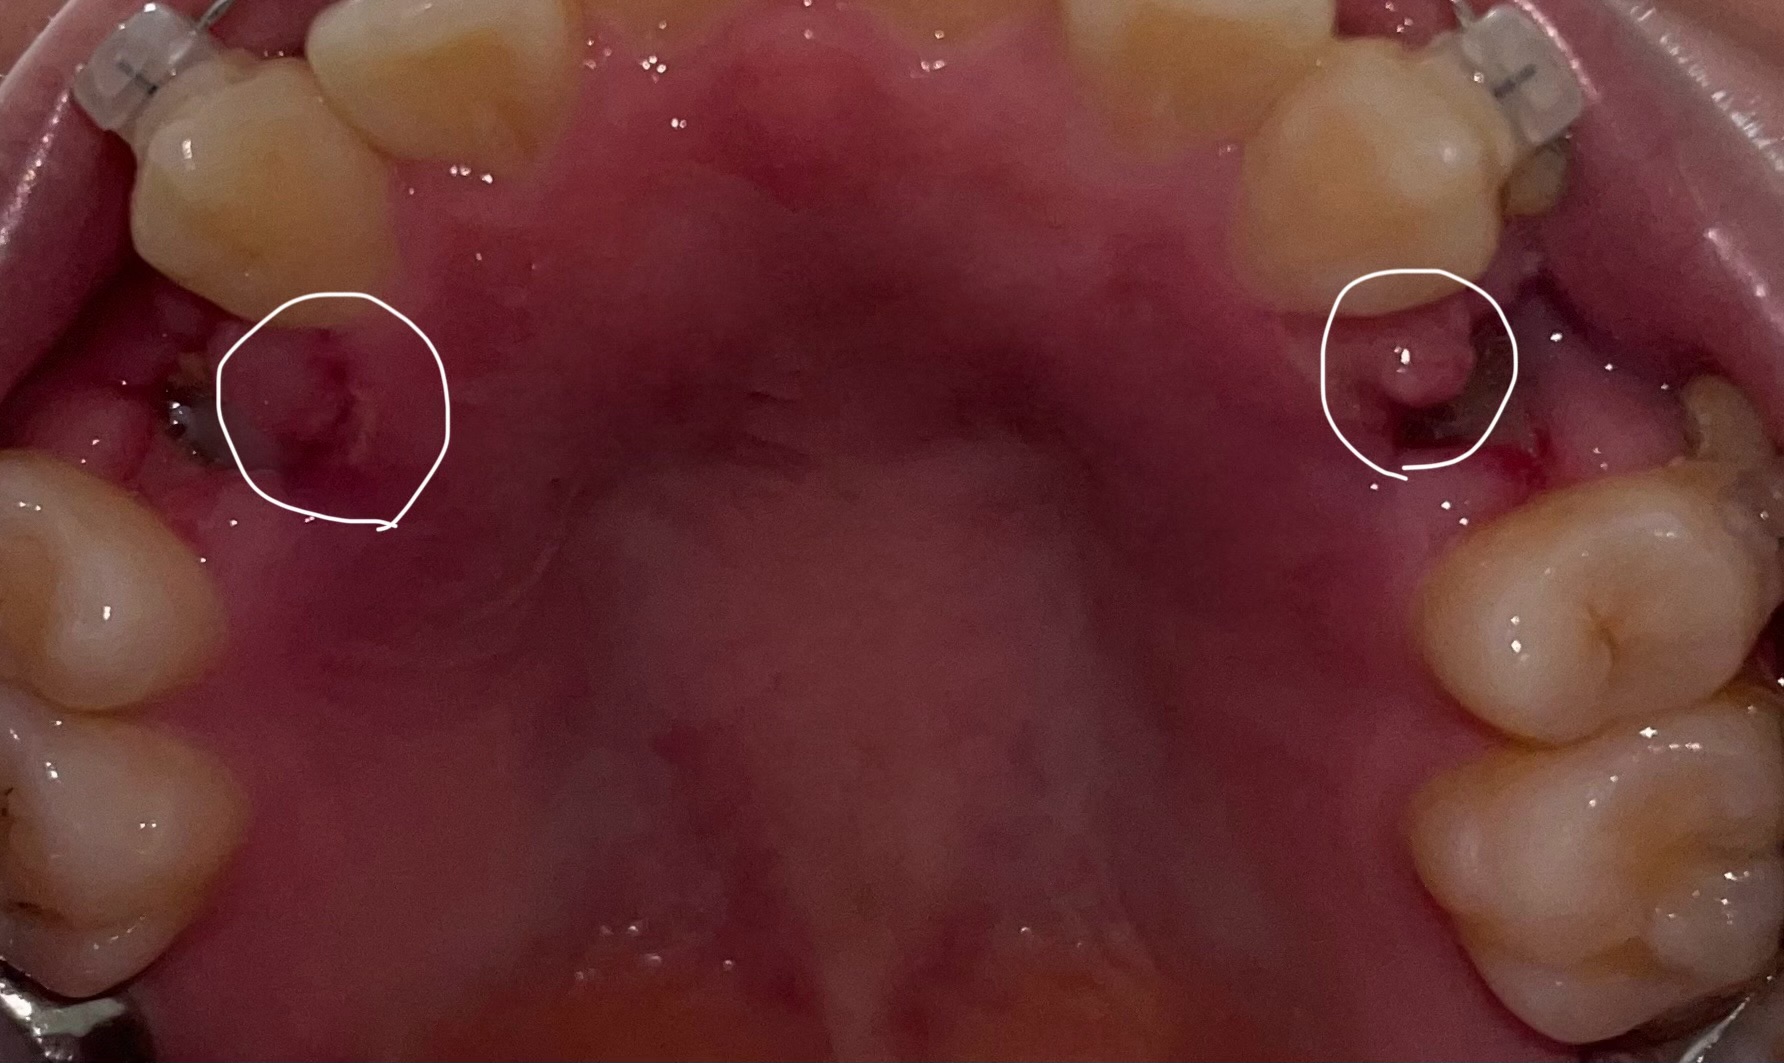

矯正のために抜歯をしましたが、痛みがひどく歯茎が腫れます。

回答数:2 -